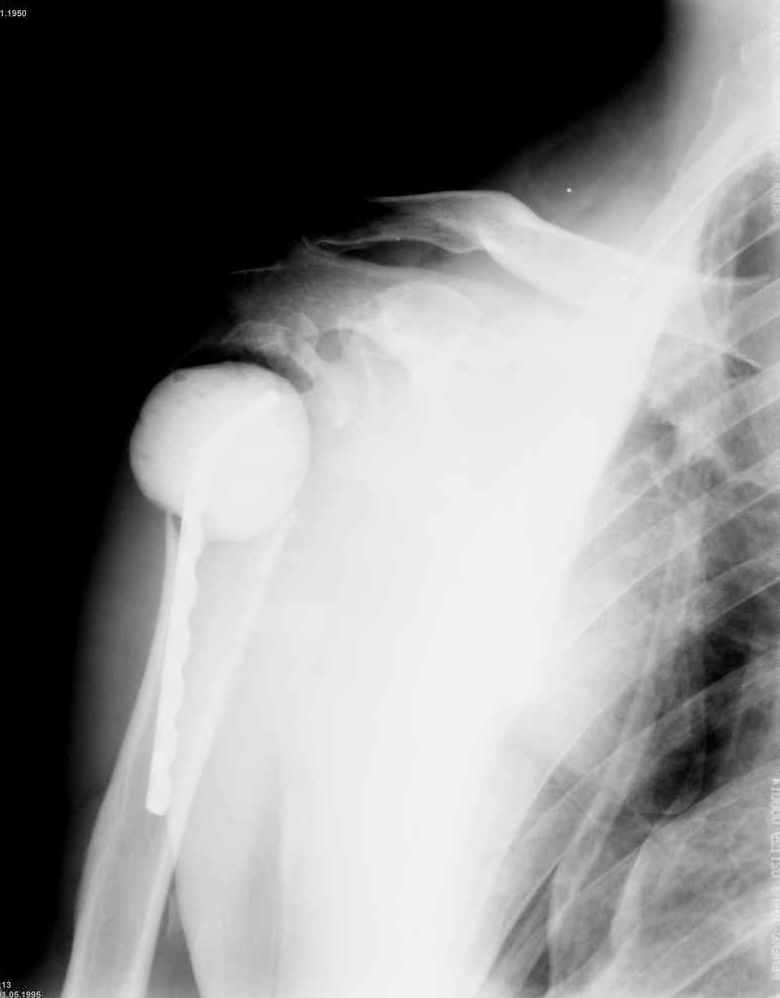

Уважаемые коллеги. Недавно из нашего отделения был выписан пациент 54 лет с закрытым переломом плечевой кости. Из анамнеза: за 2 дня до поступления в НИИСП, в состоянии алкогольного опьянения упал с лестницы на даче (высота 3-4 метра) с упором на правую руку. Через двое суток обратился за медицинской помощью. Доставлен бригадой "Скорой помощи".Правый плечевой сустав умеренно деформирован. По внутренней поверхности плеча имеется кровоподтек. При пальпации плечевого сустава имеется умеренная болезненность. Активные и пассивные движения болезненные. Снижена чувствительность по тыльной поверхности пальцев кисти и отсутствует активное разгибание кисти и пальцев. Имеется подкожная эмфизема шеи, верхней половины грудной клетки (рис 1, 2). На рентгенограмме: оскольчатый перелом головки плечевой кости со значительным смещением, перелом 2-3 ребер справа, тканевая эмфизема (рис 3). КТ при поступлении: перелом головки плечевой кости в области анатомической шейки со смещением отломка головки в грудную полость, правосторонний гидроторакс, перелом 2-3-4 ребер справа. (рис 4). Через двое суток после поступления выполнена операция: атипичная торакотомия, эвакуация свернувшегося гемоторакса, удаление инородного тела (головки плечевой кости) из плевральной полости (при этом выявлено имеющееся повреждение париетального и висцерального листков плевры) (рис. 5), дренирование плевральной полости, замещение проксимального конца плечевой кости спейсером из костного цемента с антибиотиком (рис. 6). Послеоперационный период протекал гладко. При контрольной рентгенографии положение спейсера удовлетворительное (рис. 7, 8). Дренаж из плевральной полости удален через 3 суток после вмешательства. Послеоперационная рана зажила первичным натяжением. Через 12 дней после операции больной выписан на амбулаторное лечение.

Через 3 месяца планируется повторная госпитализация для выполнения эндопротезирования правого плечевого сустава. Похожий, но менее тяжелый, случай был показан в 2004 году на сайте журнала J Bone Joint Surg Am. (http://www.jbjs.org/Image_Quiz/2004/may04/iqmay04_p1.shtml).